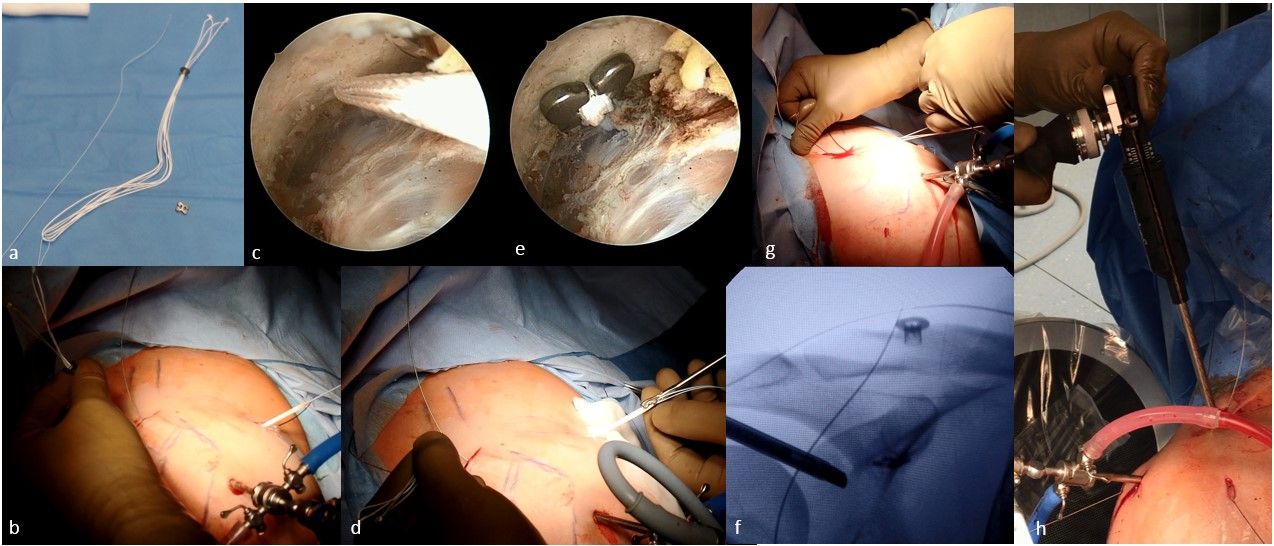

Reduction of the AC-joint and coracoclavicular stabilization

The inferior sutures of the low-profile Tightrope device (Arthrex, Naples, Florida) are attached to the proximal eyelet of the first nitinol wire and pulled from the other end through the clavicle and coracoid (Fig. 6a). Under arthroscopic control, the sutures are retrieved via the anteroinferior portal (Fig 6b & c). A DogBone button (Arthrex, Naples, Florida) is attached to the inferior sutures (Fig 6d). By using a clamp and by pulling from superior, the inferior button is placed under the coracoid arch. Under arthroscopic control, the button is placed in the correct position (Fig. 6e). By pulling the sutures of the low-profile device alternating the double button system tightens itself. The two suture pairs are pulled alternating until the superior button is on the level of the clavicle enabling an anatomical reduction of the AC-joint (Fig. 6f & g). A suture tensioner is mandatory for a proper tensioning of the Tightrope device. 80-100 N are applied for each suture which can lead to some overreduction of the AC-joint that is accepted (Fig. 6h). The anatomical reduction of the AC-joint should be controlled using the image-intensifier. Once reduction is achieved, the sutures are knotted securely. Before cutting the sutures on a low profile, to reduce knot stack, we recommend knotting the sutures of the device to provide sufficient stability and avoid early redislocations.

Acromioclavicular cerclage

For horizontal stabilization, a triangular acromioclavicular cerclage with a non-absorbable tape is used. First the tape is attached to the clavicular nitinol suture passer and pulled from the other end (Fig. 7a & b). Then the tape is attached to the eyelet of the acromial nitinol passing wire and pulled through the lateral portal (Fig. 7c). The back part of the tape at the anteroinferior portal is attached to a knot pusher device and retrieved via the clavicular incision (Fig 7d). The tape from the lateral portal is also attached to the knot pusher and retrieved subcutaneously to the clavicular incision (Fig. 7e). This step avoids soft tissue interposition. The ends of the non-absorbable tape can now be tightened and knotted (Fig. 7f).